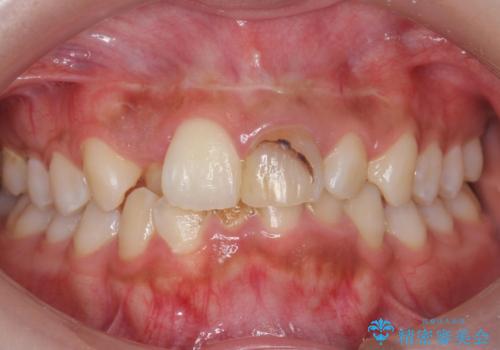

前歯の見た目が気になる。

- 前歯の見た目が気になるとの事で来院。

根の治療のやりかえは希望されなかったので土台だけやりかえを行い、ジルコニアクラウンで治療を行いました。

綺麗な被せ物が入り大変満足して頂けました。